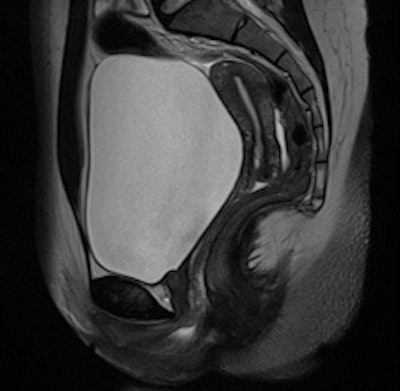

The uterine zonal anatomy and cervix are more sharply delineated on the BLADE image (right); however, SNR and CNR are higher on the conventional T2-weighted image (left). All images courtesy of Dr. Bianka Freiwald-Chilla.Previous studies have focused primarily on visual and qualitative assessment of images, so Froehlich and colleagues prospectively compared overall image quality, contrast, and diagnostic information of the recently implemented T2-weighted BLADE TSE sequence with the conventional Cartesian T2-weighted TSE sequence in female pelvic organs.

They found BLADE significantly (p < 0.0001) reduced motion and ghosting artifacts and showed improved conspicuity, but overall image quality did not differ significantly in the 47 patients who underwent sagittal BLADE and conventional TSE at 1.5-tesla after glucagon administration. In the majority of cases (53.2% versus 59.6%), radiologists preferred conventional TSE due to better image contrast and visibility of free pelvic fluid. Signal-to-noise ratio (SNR) and contrast-to-noise ratio (CNR) were significantly higher on conventional TSE.

Cervical carcinoma: The uterine zonal anatomy and bladder wall as well as the bowel loops are more sharply delineated on the BLADE image (right); however, SNR and CNR are higher on the conventional T2-weighted image (left)."Indeed, conventional T2-weighted TSE provided a significantly better visibility of free pelvic fluid or cystic structures (i.e., a relatively higher effective T2 weighting) in numerous cases," the researchers noted.